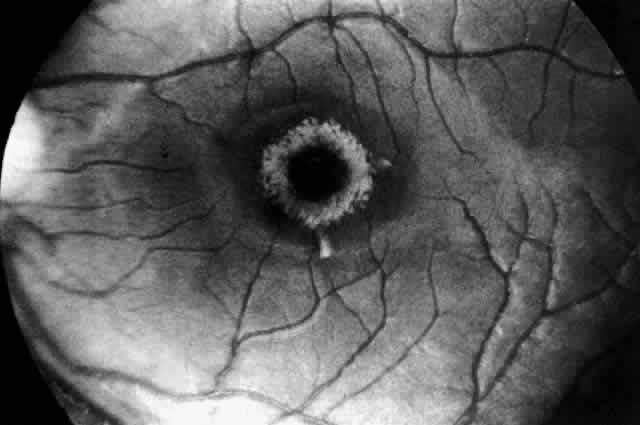

Recognition of the cherry-red spot at the macula is a major diagnostic criterion of Tay-Sachs disease (Fig. 3). It is caused by the accumulation of intracytoplasmic membranous bodies in retinal ganglion cells.

|

The circular appearance of the fundoscopic lesion reflects the anatomy of the macula. No ganglion cells are present at the very center of the macular region, the foveola, and the central red spot simply represents the normal choroidal background color. The ganglion cell layer surrounding the foveola is several cells thick, and loading of these neurons by storage products results in loss of retinal transparency and a white parafoveal halo. Peripheral to the macular region the ganglion cell layer is only one cell thick, and lipid accumulation in these cells is, therefore, less conspicuous.

Tay-Sachs disease is also the most common storage disease causing macular cherry-red spots (Table 2).3 The variation in the shade of the red spot reflects racial fundus pigmentation. The halo is opaque, slightly elevated, and 1.5 disc diameters in width. The outer border is less sharp than the inner border.

A more widespread opacification of the retina can occur due to involvement of the ganglion cells in the posterior pole. This was observed by Wray4 in a 3½-year-old child with Tay-Sachs disease. The child had black hair and brown eyes, and the cherry-red spot at the macula was brown. The patient was blind, with marked optic atrophy (Fig. 4).

A dynamic process of development of the macular cherry-red spot occurs paralleling the infant's progressive neurologic disorder. The cherry-red spot can be observed as early as 2 months of age and is conspicuous at age 4 to 6 months. Loss of visual acuity may occur without noticeable change in the circular halo. But, in time, the ganglion cells atrophy and optic atrophy and loss of the nerve fiber layer occurs. At this stage blindness coincides.